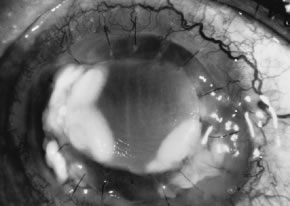

Advanced, severe filamentous fungal or yeast keratitis is indistinguishable from keratitis caused by virulent bacteria such as Staphylococcus aureus or Pseudomonas aeruginosa. The area of epithelial and stromal ulceration is large. Dense, opaque, homogenous, yellow-white stromal necrosis develop and is surrounded by confluent cellular infiltrate and full-thickness stromal edema (Figs. 19, 20, 21). Hyphal elements may penetrate Descemet's membrane and endothelium and be visualized in the anterior chamber. Fibrinous material accumulates over the endothelium, anterior chamber angle, and iris. Pain is typically severe. Secondary ocular hypertension may ensue. Progressive stromal necrosis leads to corneal perforation and, rarely, consecutive endophthalmitis.

Fig. 20. C. albicans in a woman after chronic administration of proparacaine hydrochloride drops. A. Full illumination. B. Slit illumination. Dense, homogenous suppuration is noted.

Fig. 21. C. parapsilosis keratitis in a blind eye after orbital trauma and exposure. Note the liquefactive necrosis and purulent exudates.